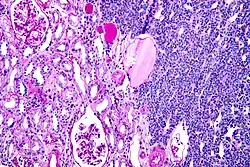

Micrograph of a metanephric adenoma with structures reminiscent of those seen in papillary renal cell carcinoma. H&E stain.

Metanephric adenoma (MA) is a rare, benign tumour of the kidney, that can have a microscopic appearance similar to a nephroblastoma (Wilms tumours),[1] or a papillary renal cell carcinoma.